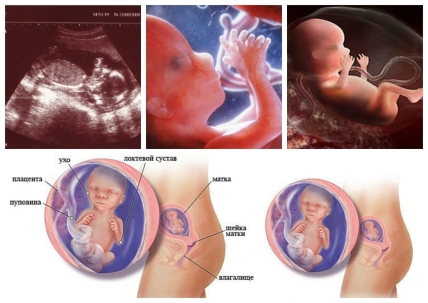

16 неделя беременности: малыш размером с небольшой грейпрут: его рост около 12 см. и вес около 100 г. Лицевые мышцы малыша уже достаточно развиты, поэтому он активно строит гримасы, хмурится и улыбается в утробе матери.

На 16 неделе беременности глаза малыша уже расположены на своем месте в передней части головы, продолжают двигаться уши, тело становится все более пропорциональным.

Активно растут нейроны крохи, их количество каждую секунду увеличивается на 5000 единиц, а надпочечники уже производят необходимое количество гормонов. У девочек на этом сроке яичники опускаются в область малого таза, сформированы фаллопиевы трубы, матка и влагалище. У мальчиков наружные половые органы сформированы, но яички еще находятся в брюшной полости.

За кроветворение отныне отвечает костный мозг малыша, также в этот период у него уже полностью сформирован состав крови: присутствуют эритроциты, моноциты и лимфоциты, можно определить группу крови и резус-фактор. В крови ребенка вырабатывается фетальный гемоглобин, обычный появится только через полгода после рождения, а сердце активно работает, перекачивая ежесекундно около 25 литров крови.

Продолжает укрепляться костный скелет малыша, становятся более развитыми ножки, почти полностью сформированы ноготки на пальчиках. Печень начала выполнять свои пищеварительные функции, также постепенно приступают к своим прямым обязанностям желудок, кишечник и желчный пузырь. Например, в кишечнике малыша появляется первое содержимое, которое пока состоит практически из желчи. Это – первородный кал, темно-зеленый или черно-зеленый меконий.

На этом сроке выполняют свое предназначение почки и мочевой пузырь крохи: каждые 45 минут малыш мочится. Моча попадает в амниотические воды, которые в течение дня обновляются около десяти раз в сутки, благодаря чему в них поддерживается стабильный химический состав, необходимый для благополучного развития плода. Сейчас количество околоплодных вод (амниотической жидкости) составляет около 250 г.

Пуповина, связывающая маму и малыша, прочная и эластичная, способная выдержать нагрузку до 5-6 кг. Ее длина к этому сроку беременности составляет уже 40-50 см, а диаметр – около 2 см.

: На этой неделе на УЗД можно увидеть, как малыш двигает глазками. Голова держится выше, шея хорошо развилась. Глаза сместились к центру (сначала они располагались по бокам), уши приблизились к своему конечному положению. Ноги удлинились и стали пропорциональнее по отношению к телу. Уже полностью сформированы ногти. Вес ребенка 130 г, длина до 12 см – размером с небольшой банан. Матка на этом сроке весит приблизительно 250 г.

Даже если будущая мама еще не ощущает движение малыша в этом периоде, полюбоваться на его кувырки она сможет во время УЗИ, ведь на экране отчетливо видно как двигается и гримасничает кроха. Также, если беременной повезет, по результатам УЗИ врач сможет ей сказать пол будущего малыша.